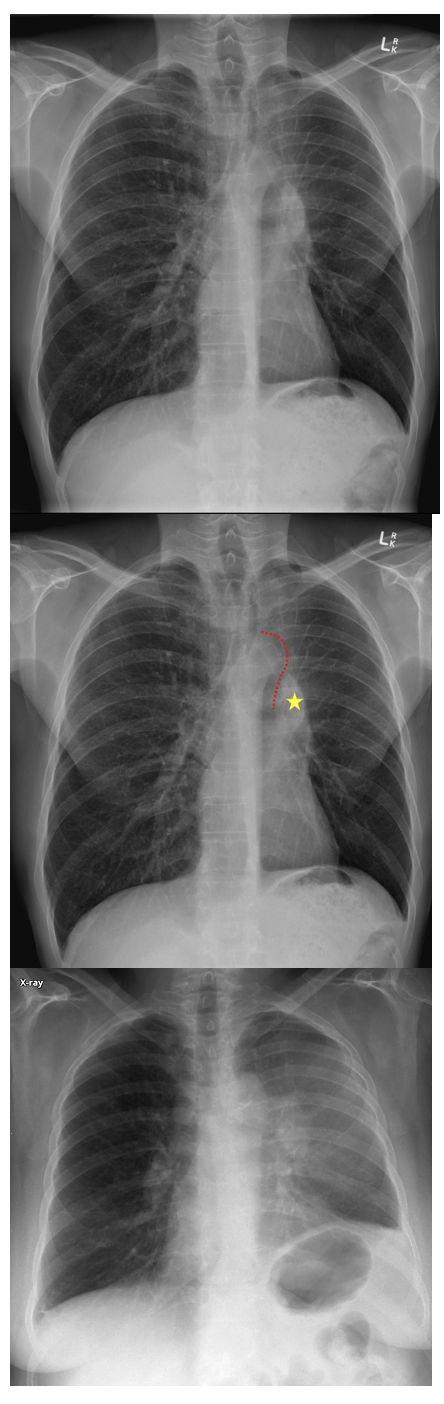

What are the RUL collapse features on CXR?

CXR features: (11)

1. Increased density in the upper medial aspect of the R hemithorax

2. Elevation of horizontal fissure

3. Loss of the normal R medial cardiomediastinal contour

4. Elevation of R hilum

5. Intermediate bronchus appears more horizontal

6. Hyperinflation of RML and LLL  increased translucency on mid and lower parts of RL

7. R justaphrenic peak

8. S shape to elevated horizontal fissure if RUL collapse combines with R hilar mass (Golden S sign)

9. Elevation of R hemidiaphragm

10. Crowding of R sided ribs

11. Shift of mediastinum and trachea to the R

What are the RUL collapse features on CT scan

CT features: (3)

Triangular opacification in axial image

Horizonal fissure rotates anteromedially

Oblique fissure bows anteriorly